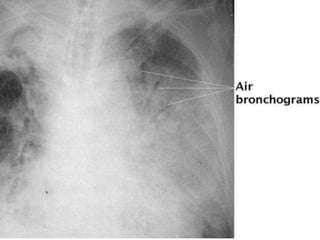

Pneumonia

• Severe pneumonia is classically manifested

by airspace disease and consolidation

(alveoli and bronchioles that are completely

filled with bacteria or other

microorganisms, white cells and

inflammatory debris)

• Air bronchograms may occur (air in larger

bronchi, outlined by consolidated

surrounding parenchyma)

Pneumonia • Severe pneumoniais classically manifested by airspace disease and consolidation (alveoli and bronchioles that are completely filled with bacteria or other microorganisms, white cells and inflammatory debris) • Air bronchograms may occur (air in larger bronchi, outlined by consolidated surrounding parenchyma)